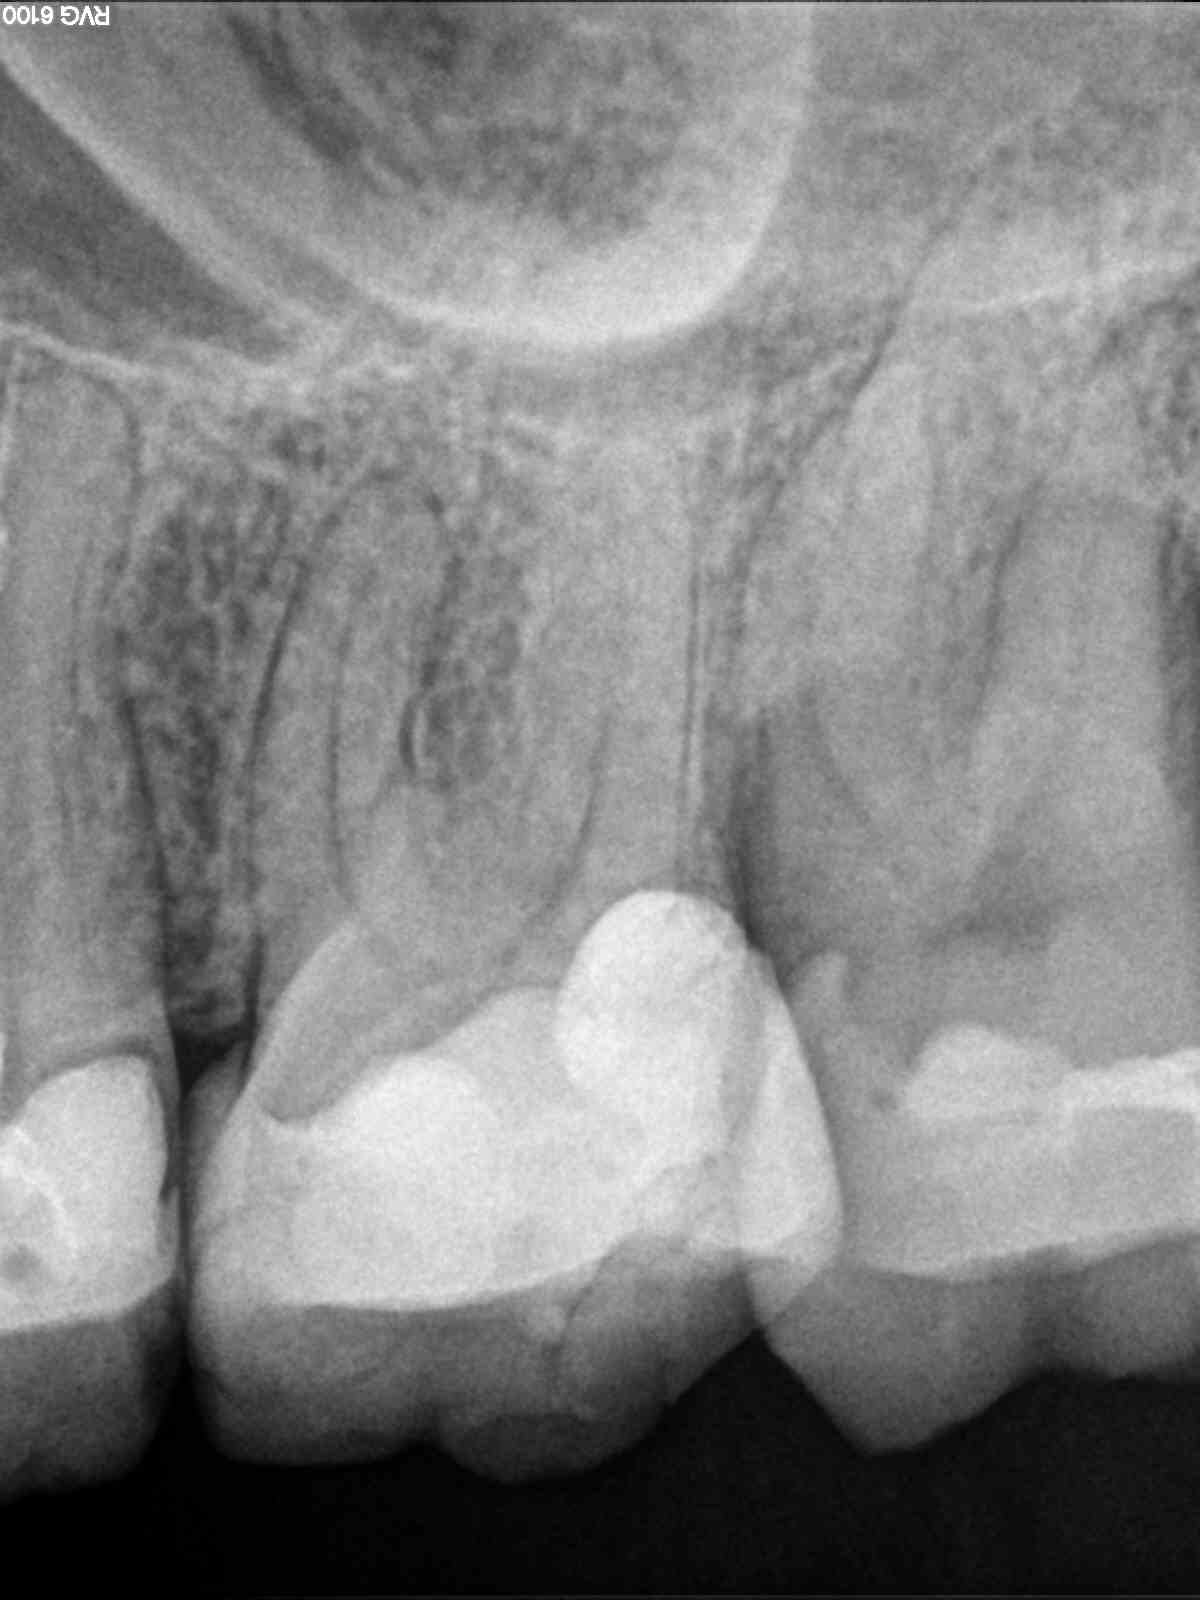

Navigierte Aufbereitung